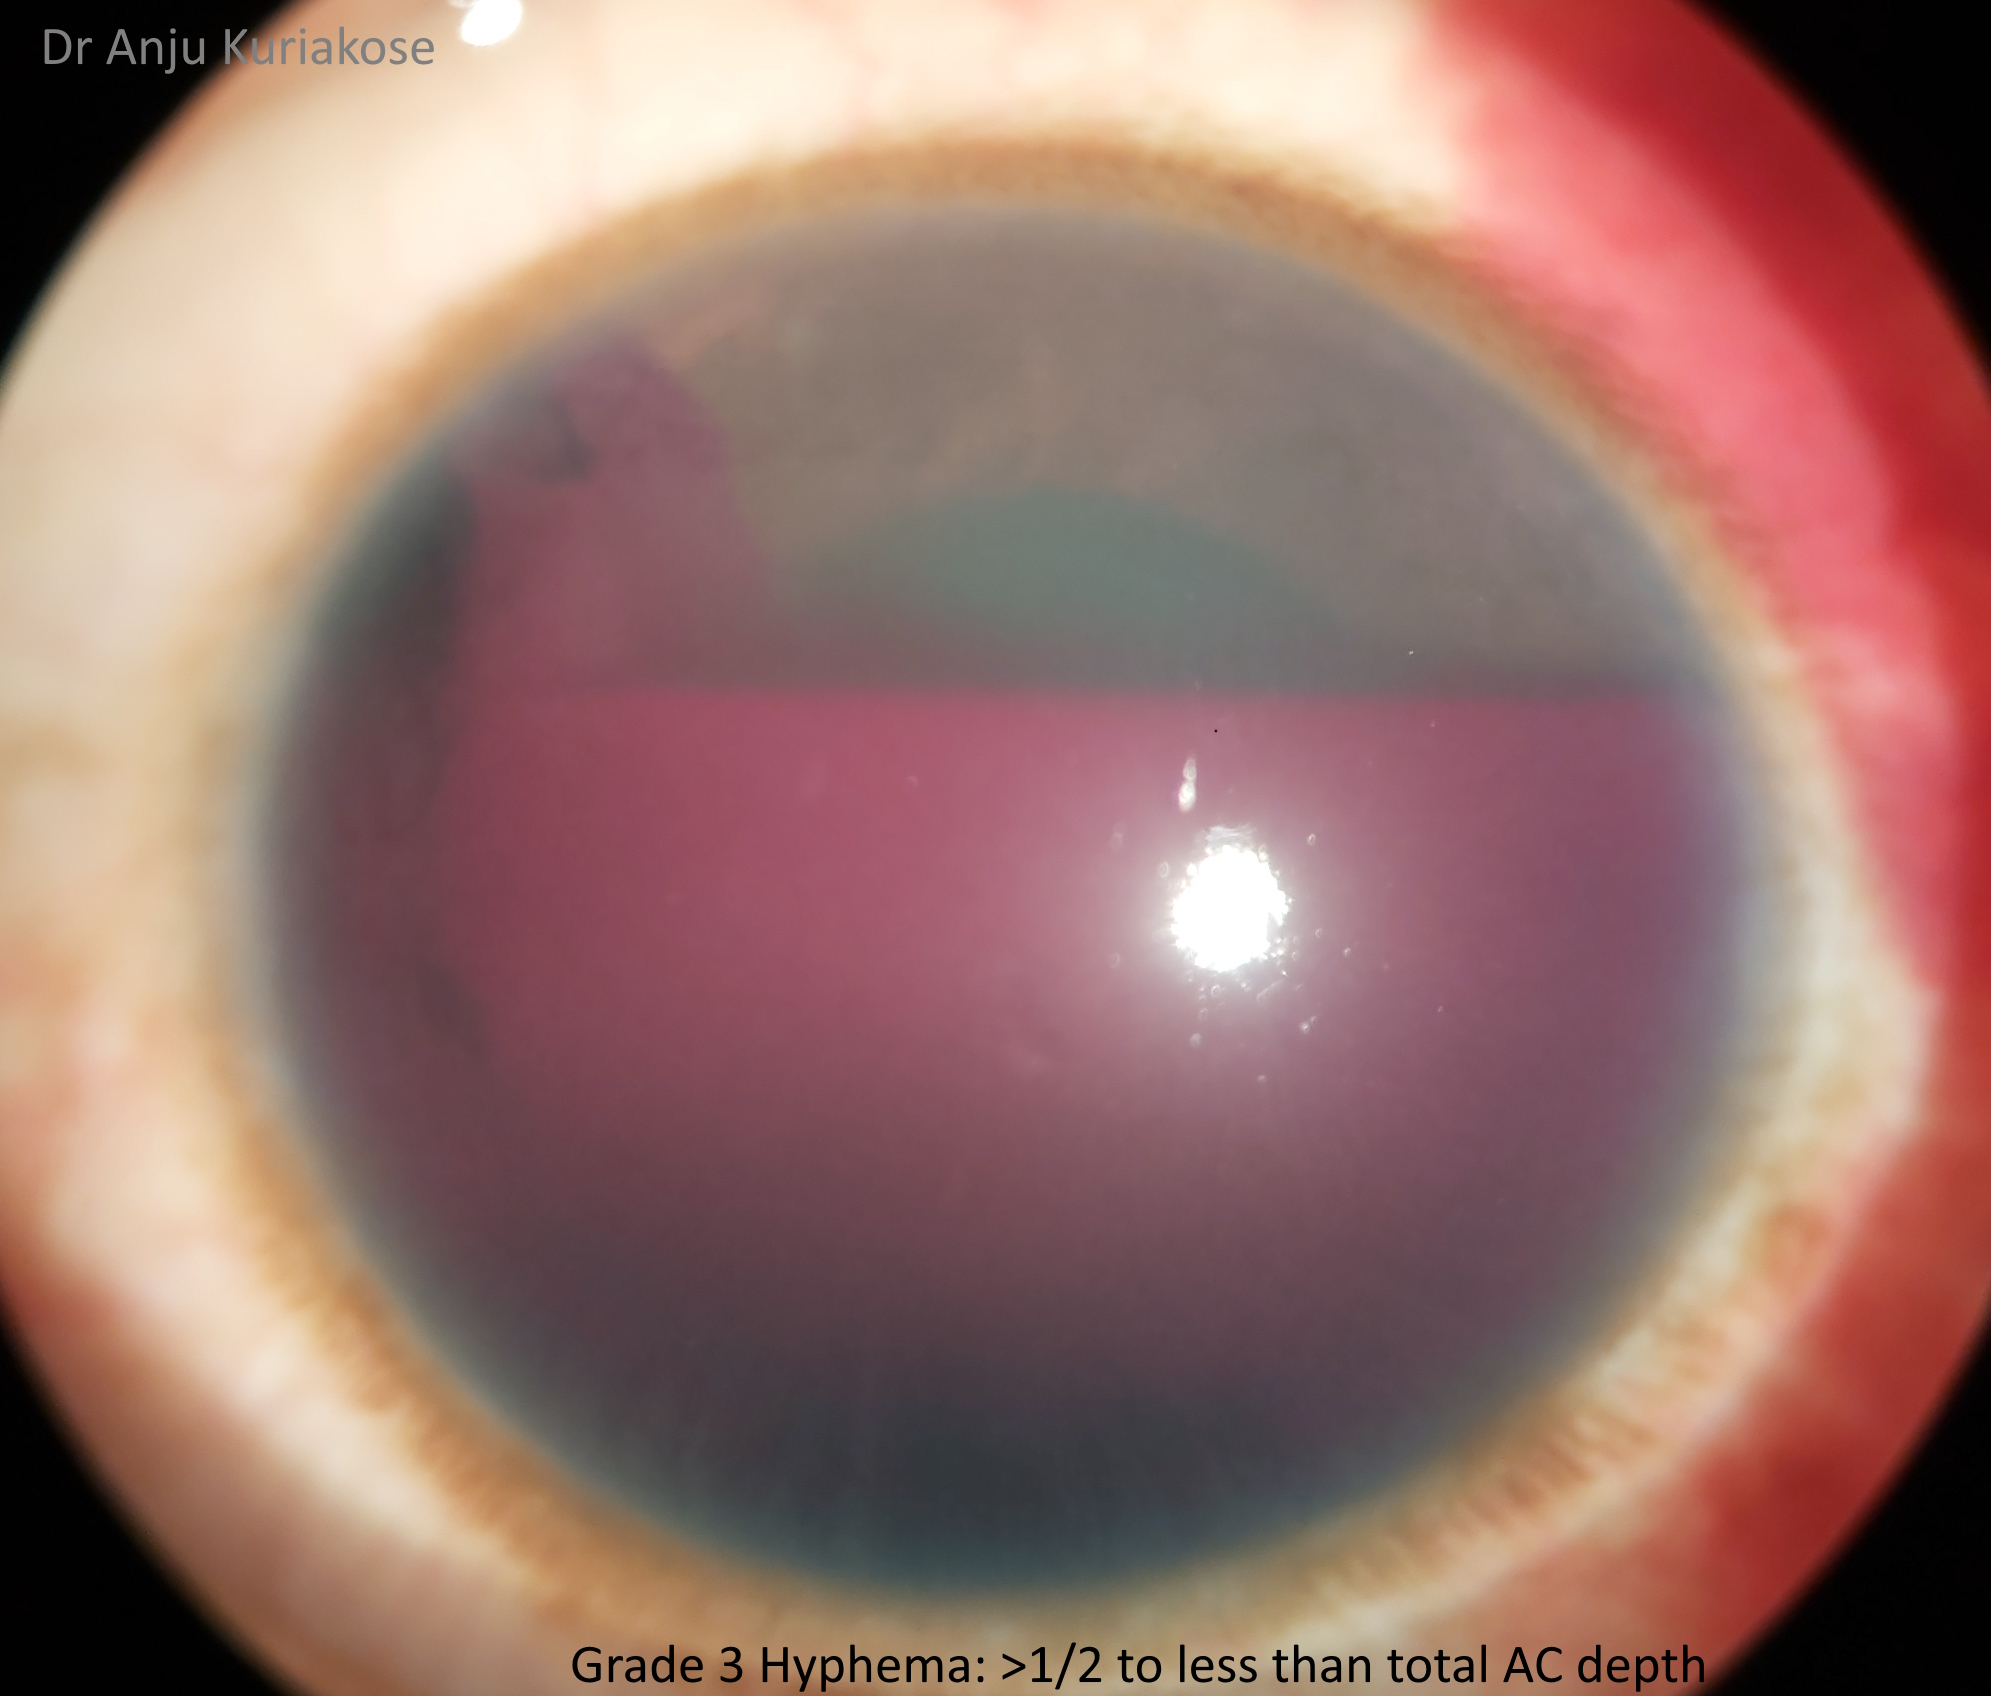

Hyphemas can be graded in the following manner:[4]

- Grade III: Layered blood fills one-half to less than total of the anterior chamber.

Grading hyphemas has value because the risk for IOP elevation increases with larger hyphemas, with the exception being in sickle cell cases where even a small amount of red blood cells can elevate IOP. Coles, in his series of 235 cases, noted that the risk of elevated IOP went up dramatically for those whose hyphemas filled more than 50% of the anterior chamber, or a grade III hyphema. Only 13.5% of those with grade I to II hyphemas had an IOP increase, compared with 27% of those with grade III hyphemas and 52% with grade IV. Also, cases with rebleeding had a more than 50% chance of having elevated IOP.[7]